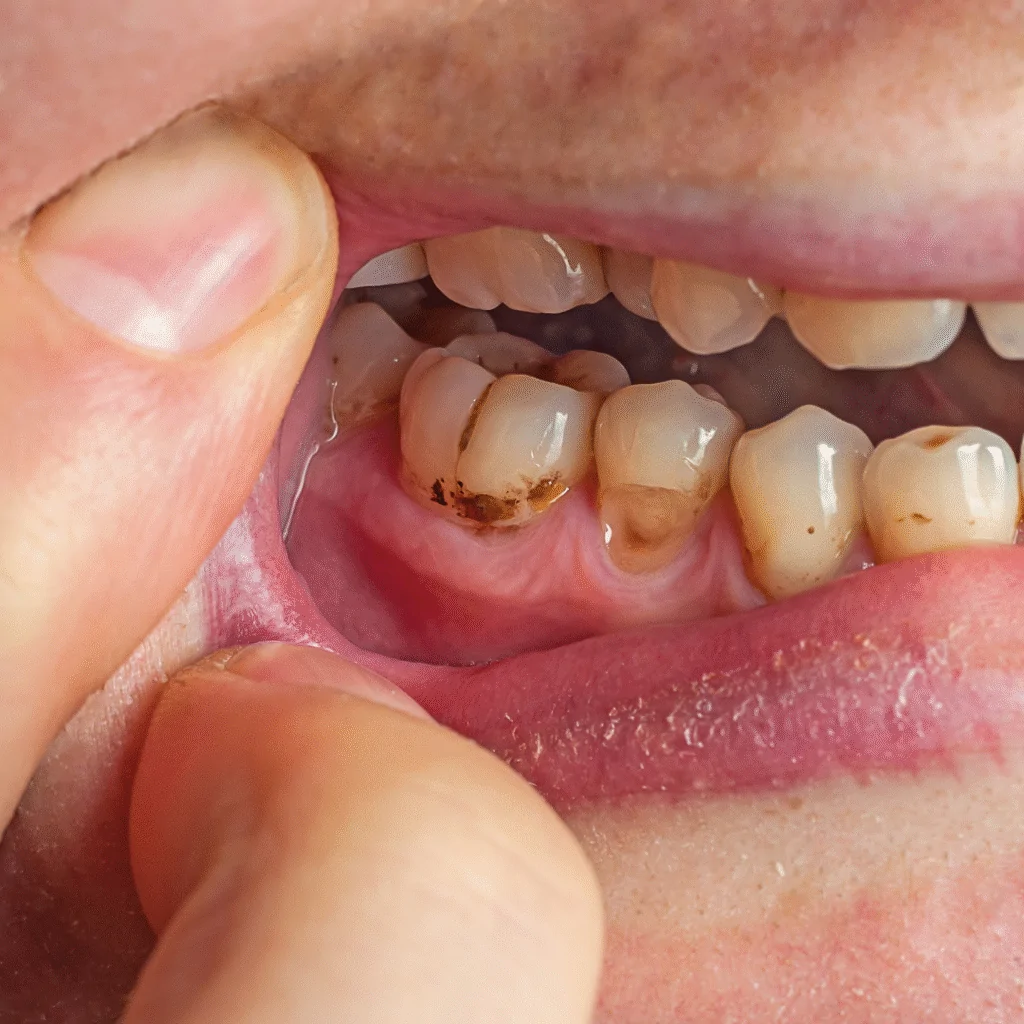

Without treatment, decay can progress deeper into the dentin and pulp, where it can cause pain and infection.

6. Worn dental restorations

Old fillings or crowns with gaps around the edges can collect plaque and bacteria.

If decay progresses, you may experience visible holes, persistent toothache, or swelling near the gum line.

Once tooth enamel is lost, it can’t grow back — but with early detection, we can preserve the remaining structure and prevent further damage.

If cavities are left untreated, bacteria can reach the inner pulp of the tooth, leading to pain, infection, or the need for a root canal. That’s why routine checkups are one of the best defences against decay.